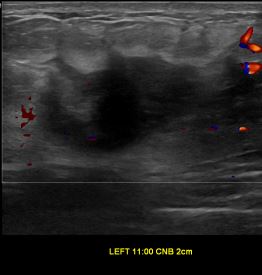

상기환자는 좌측유방 만져지는 멍우리있어  내원하신 30대중반 여성분으로 의심스러운 좌측혹 조직검사 시행해 유방암 진단되었습니다.